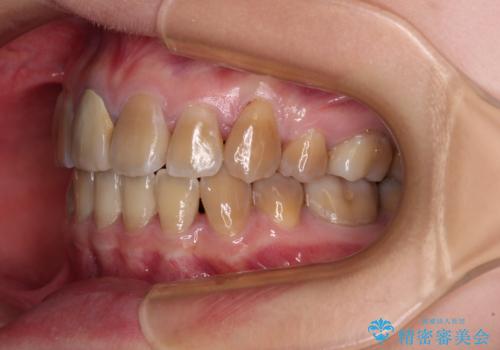

上下の正中がずれていましたが、抜歯矯正であったので、極力正中位置を合わせるように治療を進めて行きました。

顎間ゴムの使用などにより、正中位置を改善することができました。